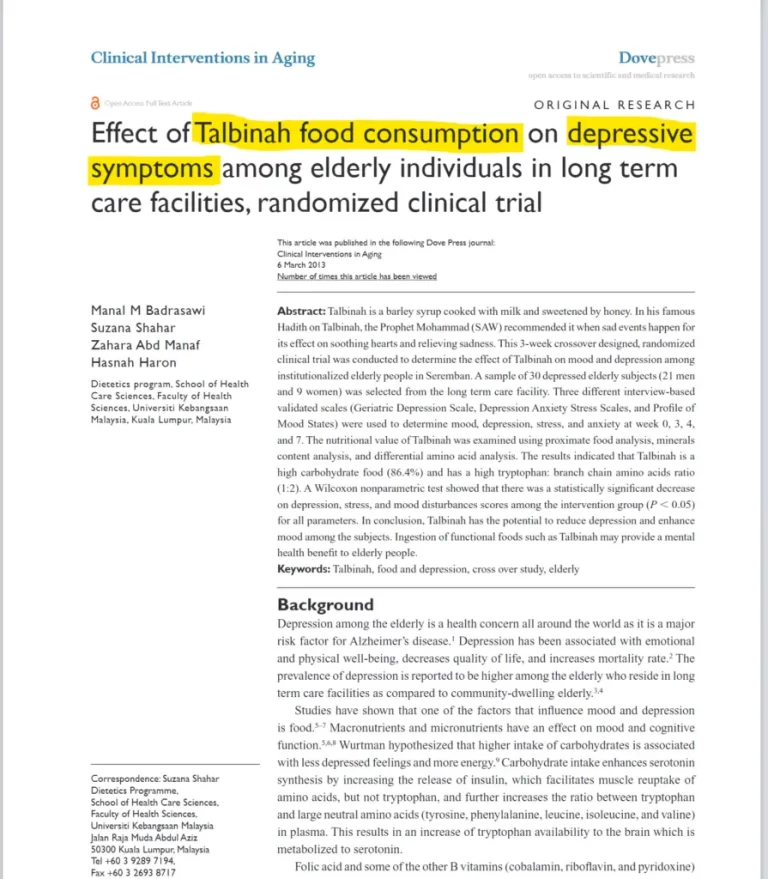

Kajian Dari Saintis UKM Dengan Amalkan Talbinah Selama 3 Minggu, Dapat Menurunkan Skor Kemurungan.